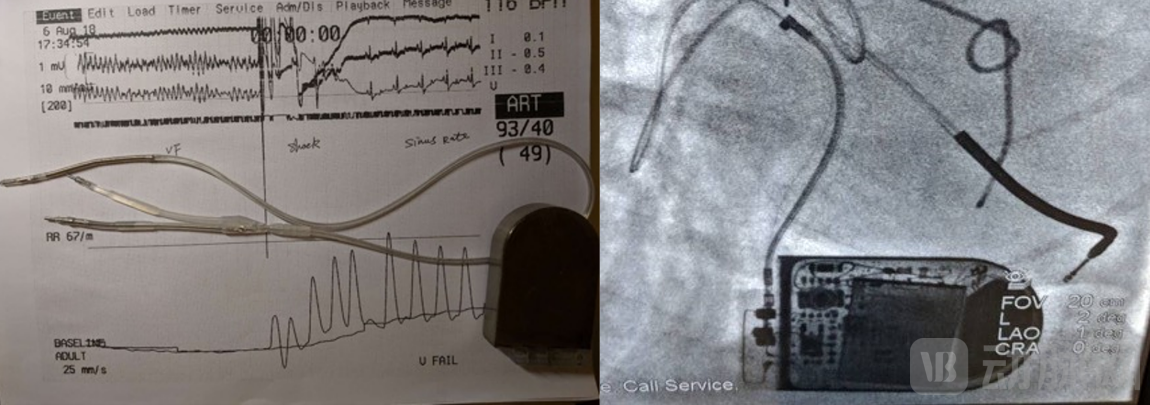

2018年8月份,在做第二次动物实验时,我们不仅实现了400MHz的无线通讯,在自己的软件界面上可以看到ICD设备传送回来的心电信号,而且我们在实验中,分别使用了车库里做出的简易的电极导线和采购的电极导线,分两次对实验狗进行诱颤除颤,都取得了成功。

第三次动物实验中,我们完成了多种方式的诱颤,测试了我们那一年重点攻关的VVI(心室起搏、心室感知、按需起搏)功能和一些高阶功能,例如小电流测试除颤阻抗等,尝试完成了一次除颤阈值的测量(DFT测试)以及多次抗体外除颤的测试。